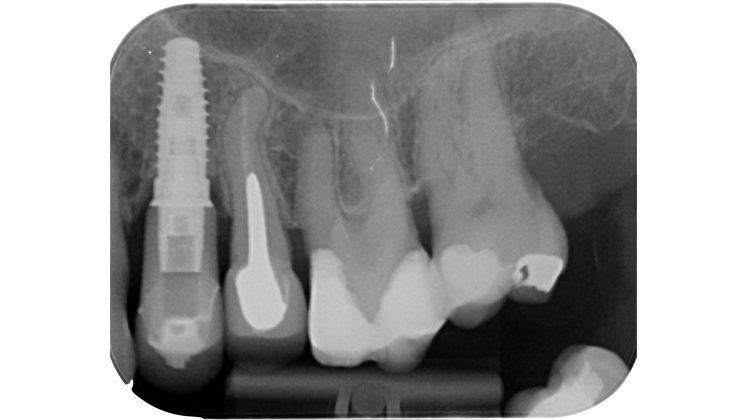

Devono essere valutate con molta attenzione la posizione dell’elemento in arcata e la sua inclinazione (Figure 6-7), l’entità e la posizione del processo carioso se presente, gli eventuali restauri posizionati sul dente e i rapporti con il parodonto: tutte queste considerazioni permetteranno al clinico di capire innanzitutto la mantenibilità e la possibilità di isolare mediante diga di gomma il dente. L’interpretazione degli esami radiografici consentirà inoltre di valutare alcuni parametri preoperatori di notevole importanza:

- presenza di radiotrasparenze periradicolari o periapicali;

- presenza di pregresse terapie canalari e valutazione della qualità delle stesse;